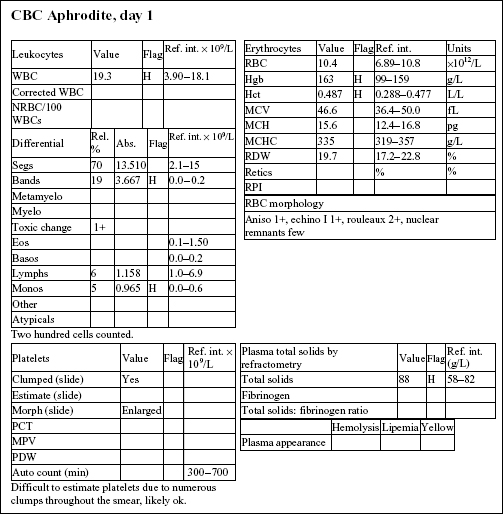

Aphrodite, a 4-year-old F(s) DLH cat, had anorexia, lethargy, and vomiting for 4 days.

The Hct and Hgb are mildly elevated and the RBC count is high normal. Total protein on the biochemical panel is high normal and there is a mild hyperalbuminemia. Total protein (solids), as measured by refractometry on the CBC, is less accurate than the biochemical determination. These findings, together with the history, suggest that the erythrocytosis is relative and due to dehydration.

There is a very mild leukocytosis, which is due to moderately increased band neutrophils and a mild monocytosis. The toxic change indicates accelerated release of neutrophils from the bone marrow. There is a significant inflammatory process, which may warrant follow-up CBC to determine if the bone marrow can continue to meet the demand for neutrophils.

Platelets often clump in feline blood samples; however, numbers are likely to be adequate in this case.

Decreases in sodium and chloride may be due to both decreased intake (anorexia) and increased losses (intestinal). However, chloride is also low relative to sodium, indicating selective chloride loss that can occur with gastric or duodenal foreign body, tumor, or swelling and inflammation leading to obstruction, or with gastrinoma (rare). The hypochloremic metabolic alkalosis also supports upper intestinal pathology. The mild hypocalcemia may not be significant. Mild urea elevation could be due to decreased renal perfusion or intestinal bleeding. Urinalysis would be required to assess renal function. Mild hyperglycemia is likely due to stress in this cat. Very mild hyperbilirubinemia may be secondary to bile stasis from anorexia or sepsis.

The CBC from day 3 is within reference limits. The absolute erythrocytosis and the inflammation were corrected with conservative therapy. Although a foreign body was suspected initially, Aphrodite recovered completely without surgical intervention.